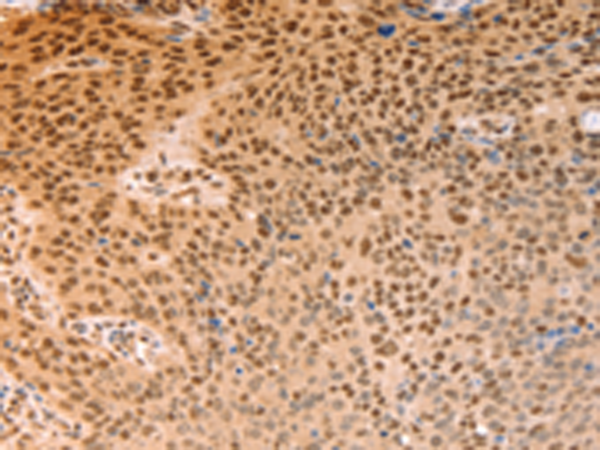

分类: 科研抗体货号: P04276别名: ALY; BEF; REF; THOC4; ALY/REF应用: IHC反应种属: Human, Mouse